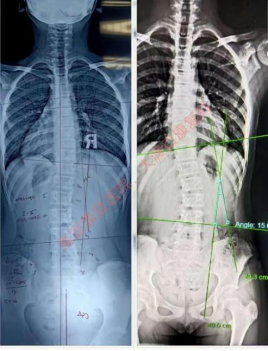

往期训练营已帮助众多青少年成功改善脊柱侧弯问题,通过治疗前后的专业对比,清晰呈现弯曲角度矫正、体态改善的显著效果,用实力护航脊柱健康。